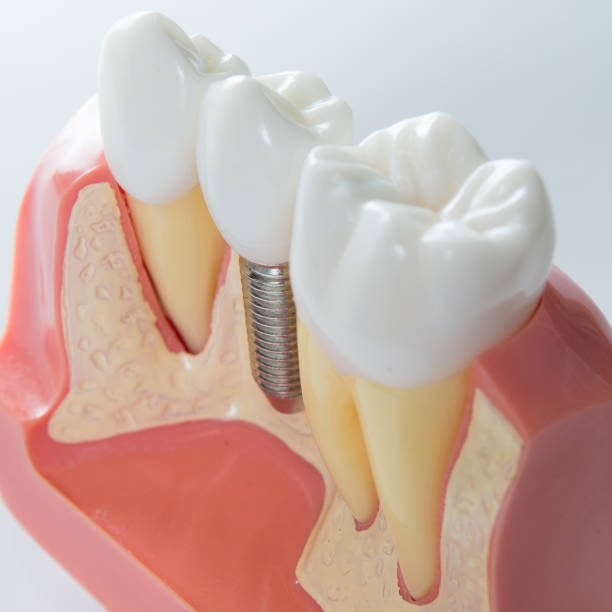

Implante

Planejamento e estudo de caso para o melhor tratamento, incluindo reposição de massa óssea

Quando fazer um implante?

Faça um implante dentário quando houver perda de um ou mais dentes devido a acidentes, doenças periodontais, cáries, infecções ou bruxismo. É indicado também para quem tem próteses desconfortáveis ou soltas, ou deseja melhorar a aparência e a mastigação. O dentista é o profissional responsável por avaliar a necessidade do implante após analisar a saúde geral e bucal do paciente.